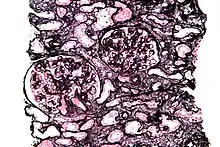

Micrograph of a kidney biopsy stained with a Jones stain.

Jones' stain, also Jones stain, is a methenamine silver–periodic acid–Schiff stain used in pathology.[1] It is also referred to as methenamine PAS which is commonly abbreviated MPAS.

It stains for basement membrane and is widely used in the investigation of medical kidney diseases.

The Jones stain demonstrates the spiked GBM, caused by subepithelial deposits, seen in membranous nephropathy.